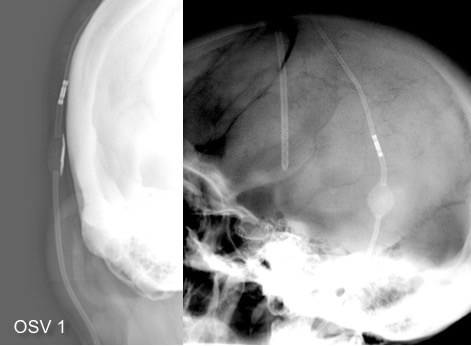

il existe un grand nombre de valves ; il n’est pas toujours aisé de les reconnaitre radiologiquement. voici la liste des plus courantes :

comment reconnaitre radiologiquement le type de valve ?

il est important pour le radiologue qui fait une IRM quel est le type de valve en raison des implications sur l’image et sur le fonctionnement de la valve (en pratique ce surtout les anciennes sophysas ancien modèle qui se dérèglent dans l’IRM).